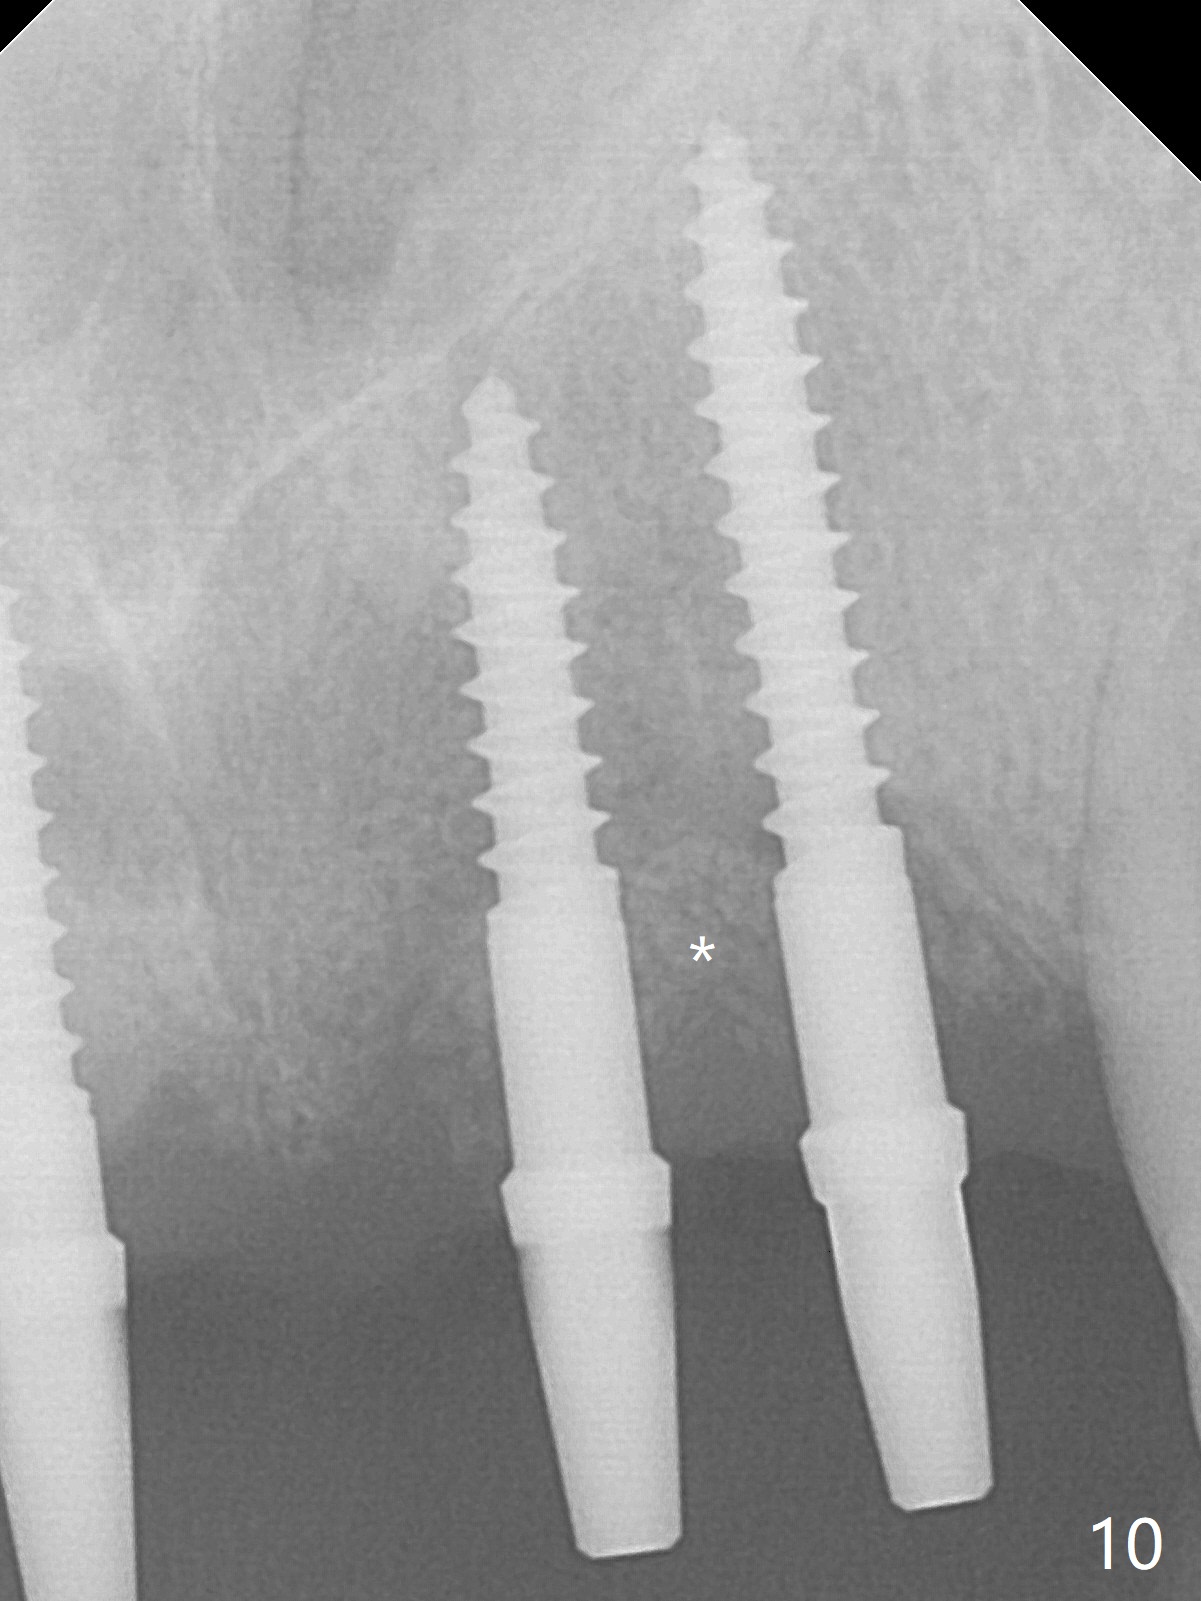

Although the ridge of the maxillary anterior ridge looks moderate in width (Fig.1), the bone is ~4 mm buccopalatally. Suction down surgical stent (Fig.2') made from the lab-fabricated provisional (Fig.2) will be used to check the position and trajectory of osteotomies. PAs taken after initial osteotomies (1.2 mm drill) show those at the central incisors tend to be mesial (close to the Incisive Canal *), while those at the lateral incisor sites distal (Fig.3,4). After adjustment, the position and trajectory of the osteotomies are acceptable (Fig.5,6). To reduce the chance of perforating the Incisive Canal (Fig.3,4 *), 2.5 mm 1-piece implants are inserted with >40 Ncm (Fig.7,8). After deep placement of the implants, Vanilla graft is placed at the crest (Fig.9,10 *). An immediate splinted provisional is fabricated from the suction down stent. The gingiva is healthy around the provisional (Fig.11) and the implants (Fig.12,13) 1 month postop. The provisional is adjusted monthly so that the interdental papillae can be elongated. No bone resorption is observed 6 months postop (Fig.14,15). Crowns are cemented 8 months postop (Fig.16-18). The keratinized gingiva appears to have formed the abutments 8 months postop immediately pre-cementation (Fig.19).